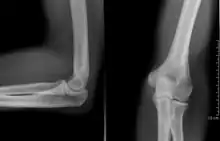

![]() Projectional radiography of the knee in a modern X-ray machine | |

Projectional radiography

The creation of images by exposing an object to X-rays or other high-energy forms of electromagnetic radiation and capturing the resulting remnant beam (or "shadow") as a latent image is known as "projection radiography". The "shadow" may be converted to light using a fluorescent screen, which is then captured on photographic film, it may be captured by a phosphor screen to be "read" later by a laser (CR), or it may directly activate a matrix of solid-state detectors (DR—similar to a very large version of a CCD in a digital camera). Bone and some organs (such as lungs) especially lend themselves to projection radiography. It is a relatively low-cost investigation with a high diagnostic yield. The difference between soft and hard body parts stems mostly from the fact that carbon has a very low X-ray cross section compared to calcium.